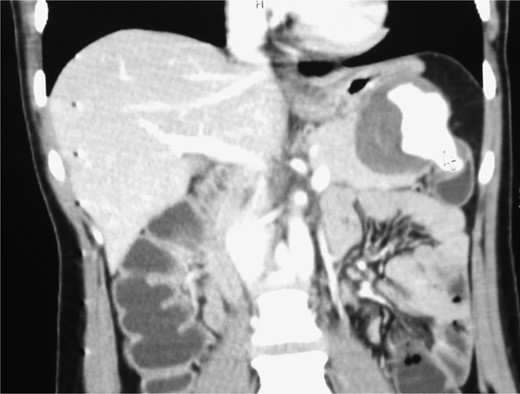

A triphasic, contrast enhanced computed tomography (CT) scan revealed a 6 cm × 5.2 cm well defined, heterogeneous, hypodense mass arising from the pancreatic tail, with an extremely enhancing component (200 Hounsfield units) on its lateral side, a feeder vessel arising from the splenic artery and a small splenic infarct (Fig. 1). Fascial margins of the mass were poorly defined from the splenic hilum and splenic flexure of the large intestine (Fig. 2). CT imaging was supportive of a differential diagnosis of a solid pseudopapillary tumor of the tail of the pancreas with invasion of the colonic wall and compression of the stomach.

CT image showing the ‘ying yang’ sign of the SAA. White arrow shows the origin from the splenic artery. Black arrow shows a splenic infarct.